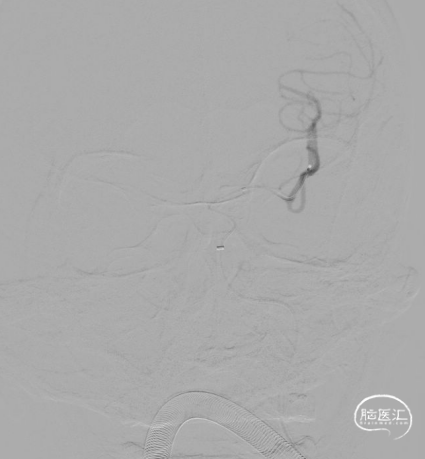

全身麻醉,右侧股动脉入路,应用泥鳅导丝、单弯造影导管辅助下将6F 90cm长鞘置于左侧颈总动脉末端,继续在泥鳅导丝及该长鞘辅助下将6F 125cm 通桥银蛇®颅内支持导管置入右侧颈内动脉C3段、长鞘置于颈内动脉C1段,然后在路图下,0.014" 北斗SS™神经血管导丝引导下将微导管小心通过闭塞段置于右侧大脑中动脉上干M2段,并造影确认真腔。

然后经该微导管置入通桥蛟龙®取栓支架 6.0*30mm,于闭塞段定位并完全释放;造影见血管较前恢复通畅。